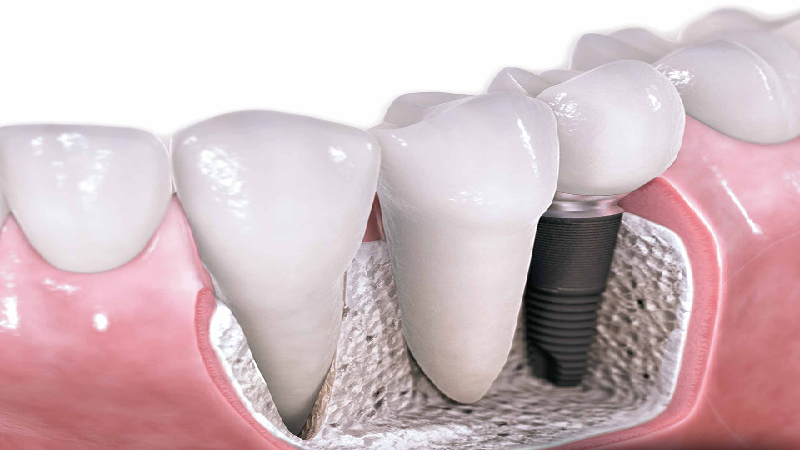

- ایمپلنت دندان اصفهان

شناخت عوامل بروز شکست ایمپلنت دندان

مرا حل اولیه و تاخیری شکست ایمپلنت دندان

در دو مرحله ممکن است شکست ایمپلنت اتفاق بیافتد و بدن آن را پس بزند. مرحله اول طی 3 تا 4 ماه بعد از عمل ممکن است اتفاق بی افتد. برخی از علل و عواملی که باعث پس زدن ایمپلنت در مراحل اولیه می شوند عبارتند از:

ایمپلنت ناموفق دندان به صورت تاخیری هم از 1 تا 10 سال بعد از فرآیند ایمپلنت گذاری دندان اتفاق می افتد و می تواند ناشی از موارد زیر باشد:

سایر عوامل تاثیرگذار بر روی شکست ایمپلنت دندانی

در حالی که پری ایمپلنتیت و عدم موفقیت استئواینتگریشن دو عامل اصلی در عدم موفقیت ایمپلنت هستند، دلایل و علل زیر نیز می توانند در این شکست دخالت داشته باشند: